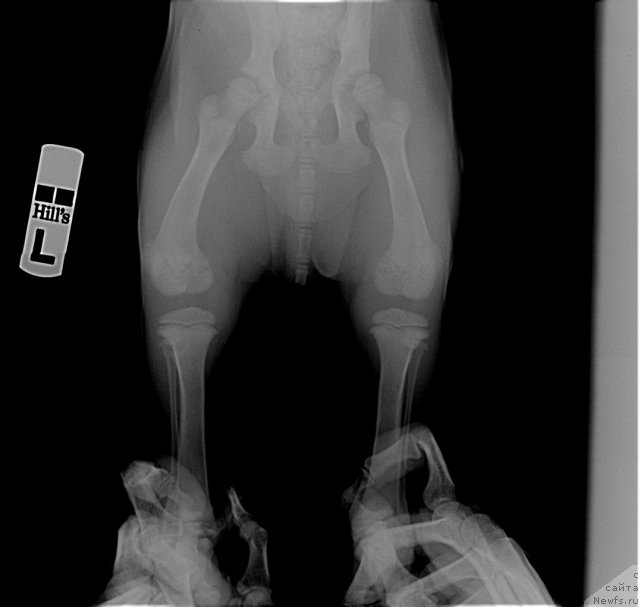

Посмотрите на суставы 2-х месячного щенка лабрадора. Насколько большие ростовые зоны. Какие огромные расстояния между костями суставов. И насколько еще не сформированны суставы. Особенно локтевые. А это собака гораздо легче ньюфаундленда. На него просто наступила сука. И такие травмы.

Фотография № 116289

Фотография № 116290

Фотография № 116291

А это рентген суставов месячного щенка.

Фотография № 116297